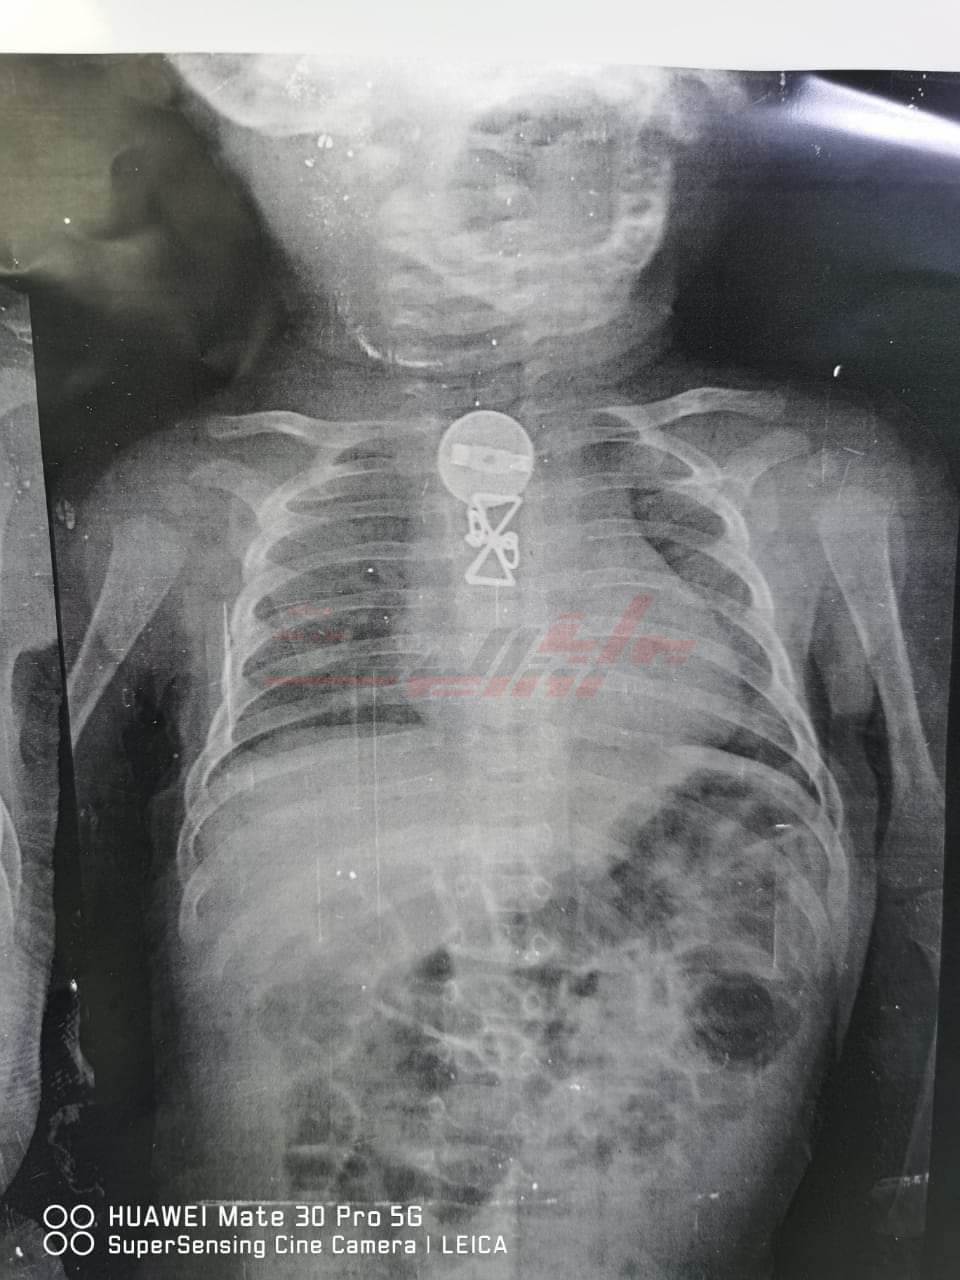

وأشار رئيس الفريق الطبي، إلى أن المستشفى استقبل الطفل وكان يعاني من التنفس وتم حجزه بالمستشفى وعمل الأشعات اللازمة، وتبين وجود جسم معدني داخل الجسد، وتم استخراجه، وتم العرض على والديه اللذين أقرا أن شقيقته الكبرى كانت تداعبه، وقام ببلع ذلك الجسم المعدني منذ فترة.